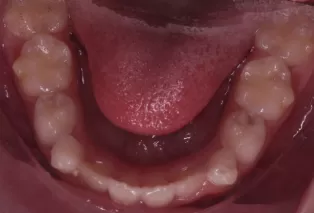

Intraoral photos